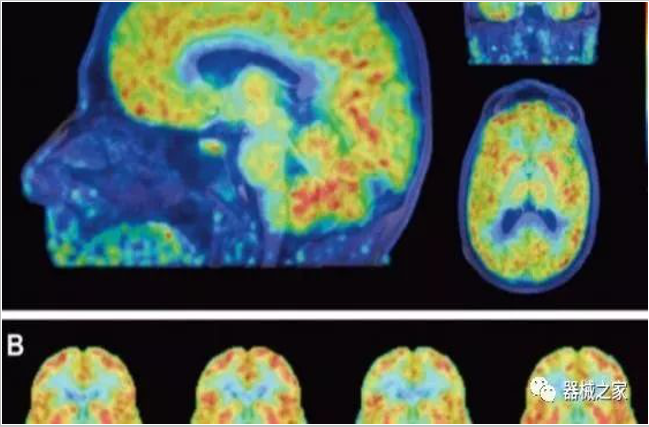

正電子發(fā)射型斷層儀(Positron Emission Tomography, PET)是對正電子示蹤劑的探測設備,具有極高靈敏度和精準的定量功能。而PET/CT是將PET與CT有機結合起來(lái)的融合設備,已經(jīng)成為腫瘤、神經(jīng)和心血管系統疾病診斷,臨床分期和療效評估的最佳影像技術(shù)。

PET掃描顯示成年女性大腦比男性年輕三歲!